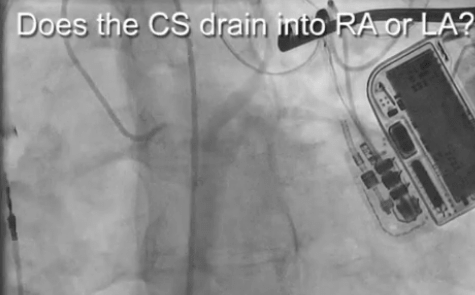

Levophase CS venography in Pt with Unroofed CS no PVOM needs redone with audio

Levophase CS venography Unroofed CS with PVOM

Levophase CS venography with CSA & PVOM